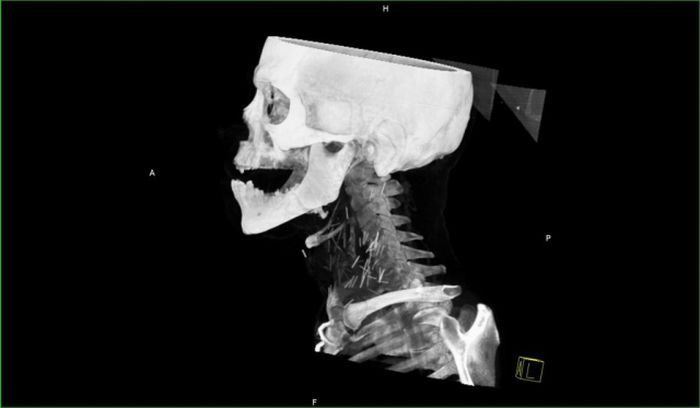

Рентген показал, что у чувака в шее огромное количество иголок.

Оказалось, что товарищ - нарк со стажем и все эти иглы остались в шее после неаккуратных инъекций.

Парня подлечили, конечно. Но иглы он отказался вытаскивать, так как он их типа любит и привык к ним.